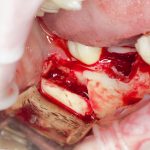

Забор костного фрагмента проводится с наружной косой линии с помощью ультразвукового пьезохирургического инструмента. Ничего сверхнового и супернеобычного тут нет, совершенно стандартная методика. С той лишь разницей, что молоток для этого используют только фашисты и только в гестапо использовать не нужно, всё делается усилием и ловкостью рук.

Нюансы начинаются с обработки принимающего ложа. Да-да, уважаемые друзья, одна из причин некроза блоков, их чрезмерной атрофии и прочих проблем — в отсутствии обработки принимающего ложа. Некоторые делают дырки, но правильнее и эффективнее поступить так:

то есть, просто снять слой кортикальной пластинки с участка, к которому будет фиксироваться костный блок. Почему? Читайте здесь>>.

Вторая особенность — мы не адаптируем и не обрабатываем костный блок invitro, а фиксируем его так, как есть:

после чего обрабатываем — доводим до окончательной формы альвеолярного гребня:

Далее, можем приступить к установке имплантатов. Разумеется. по хирургическому шаблону:

Последняя картинка даёт представление о том, какой объем костной ткани мы «нарастили».